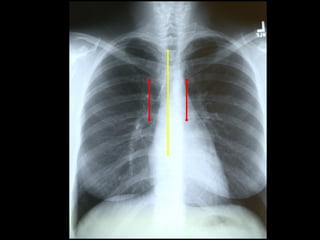

Medial ends of

bilateral clavicles

are equidistant from

the midline or

vertebral bodies

If spinous process appears closer to the right clavicle (red

arrow), the patient is rotated toward their own left side

If spinous process appears closer to the left clavicle (red arrow),

the patient is rotated toward their own right side